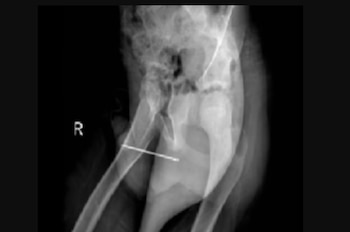

Sin embargo, también señalaron que el niño no tenía antecedentes de problemas de salud mental. Aunque los detalles del caso son escasos, se informó que los rayos X mostraron el objeto afilado en una posición que dificulta su extracción utilizando métodos normales, como empujarlo fuera del pene por la misma uretra

Después de darle al niño anestesia para adormecer el área, empujaron manualmente el extremo romo de la aguja hasta que la punta afilada penetró en la piel y lo sacaron por ese orificio.